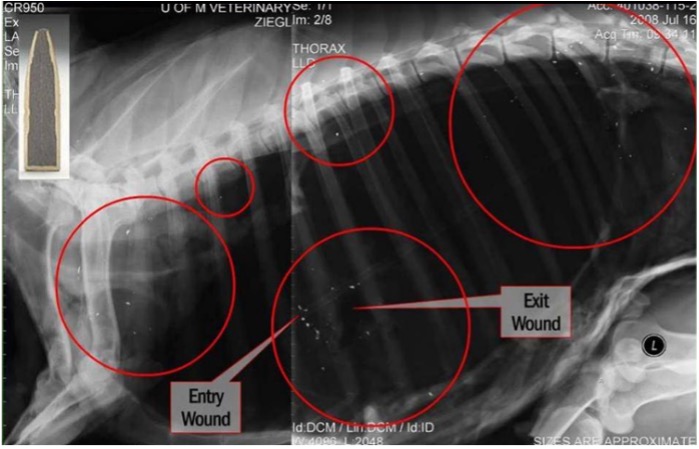

When an animal is shot with lead-core bullets, as much as a third or more of the bullet's total weight can be fragmented into hundreds or even thousands of tiny pieces upon impact and remain inside the body. When gut piles or parts of animal carcasses that were shot with lead bullets remain (or are placed) in the field, lead fragments often are left with it. Scavenging wildlife such as bald eagles, golden eagles, crows, and foxes can unintentionally ingest these fragments when scavenging remains. For some species, even after ingesting a tiny amount of lead, lead poisoning can occur, causing neurological and motor impairments that can lead to death or long-term impairment within a matter of days or over a long period of time.

After years of development, today's copper bullets are available in a large array of calibers, weights, and designs that meet or exceed the performance of their lead counterparts. While some lead bullets can lose up to 40% of their mass on impact, spraying into tiny fragments up to 18 inches from the wound channel, copper bullets typically retain 95 to 100% of their mass, which can improve bullet penetration with a similar wound channel.

Yes, lead bullets begin fragmenting just after impact and continue to shed fragments as they pass through the animal. Rates of fragmentation vary depending on bullet construction, but any amount of lead can unintentionally impact scavenging wildlife.